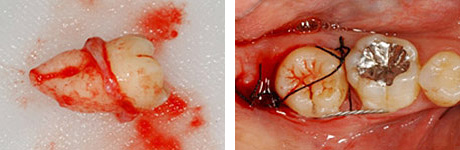

左:移植のために抜歯された親知らず(ドナー歯)。

右:移植直後。